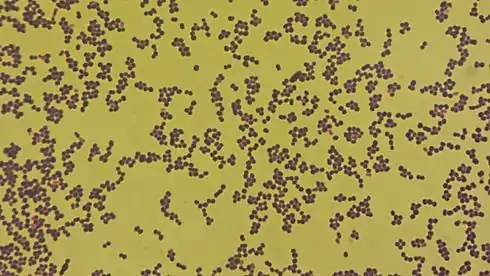

Aerococcus urinae is a type of bacteria that can lead to infections in the urinary system. This work describes a 73 year old man who had an infection with Aerococcus urinae. Samples of blood and urine were taken from the patient, and when put on blood cells the bacteria weakly changed the color of the blood cells around them. This result is called alpha hemolysis, and can be seen in Image 1. Adding Gram stain to the bacteria turned them violet, and therefore the bacteria were Gram-positive. This can be seen in microscopy in Image 2. The patient was treated with antibiotics. Full text | Download doi: 10.15347/WJM/2015.001